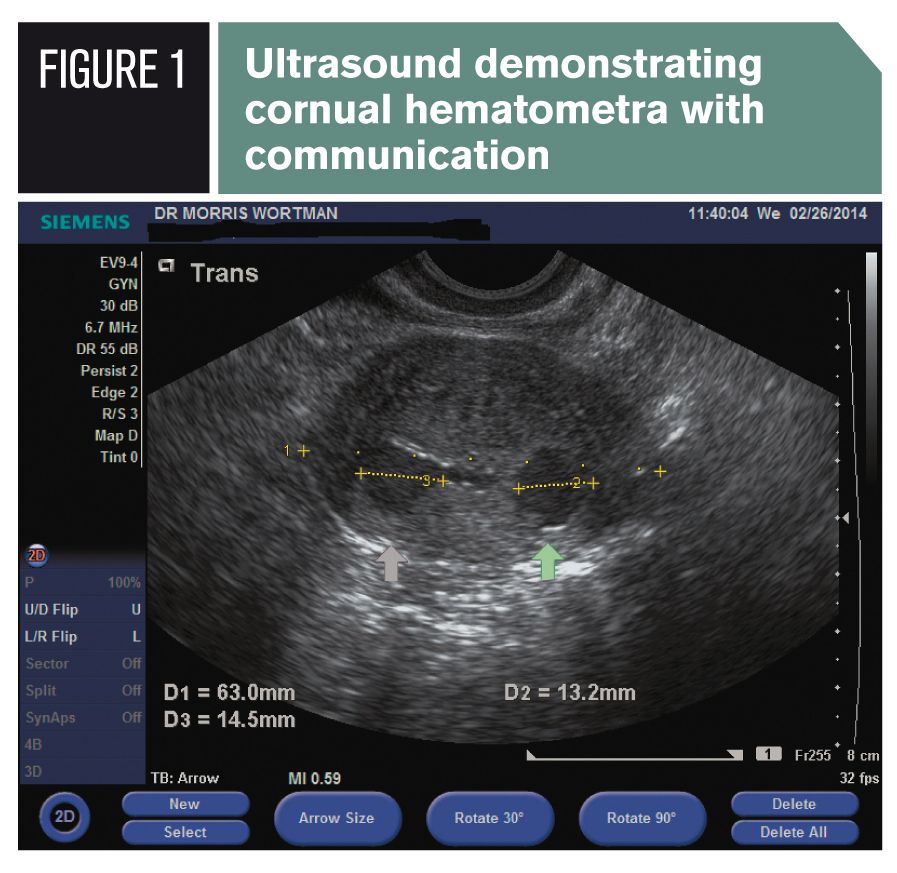

Frequency Of Symptomatic Cornual Hematometra And Postablation Tubal Sterilization Syndrome After Total Rollerball Endometrial Ablation A 10 Year Follow Up American Journal Of Obstetrics Gynecology